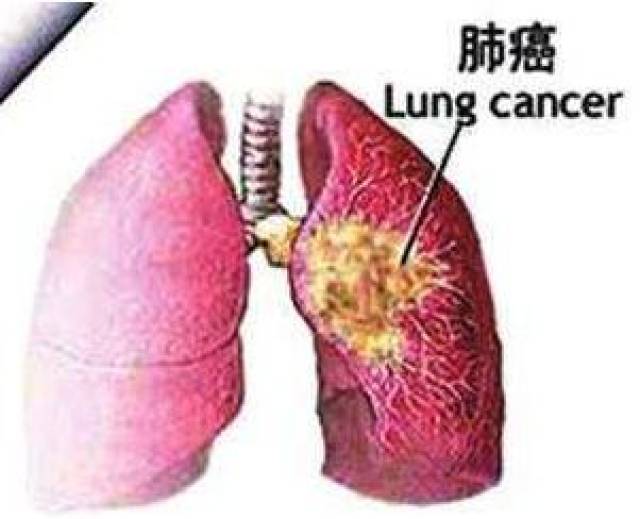

- 肺癌患者的肺(左图)与正常人的肺(右图)的比较